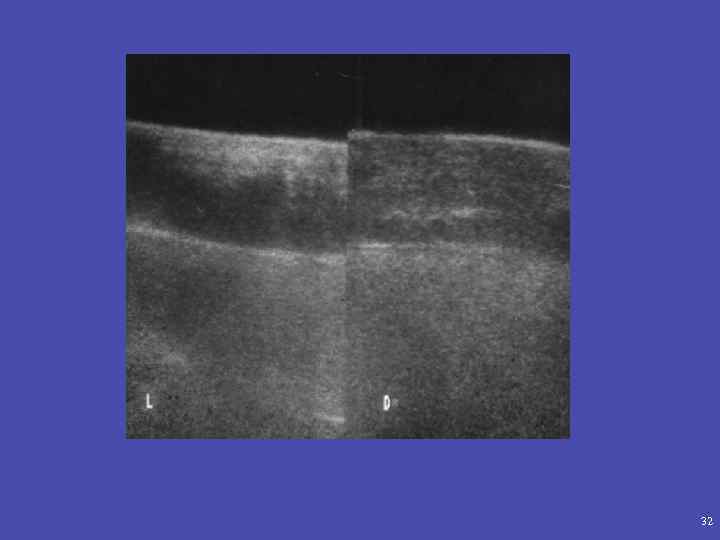

32

Отек мягких тканей визуализация надкостницы визуализация скопления гнойного субстрата между надкостницей и кортикальным слоем кости Больной Б. 12 лет. Остеомиелит правой плечевой кости. Длительность трое суток. Гиперэхогенное образование – абсцесс. 33